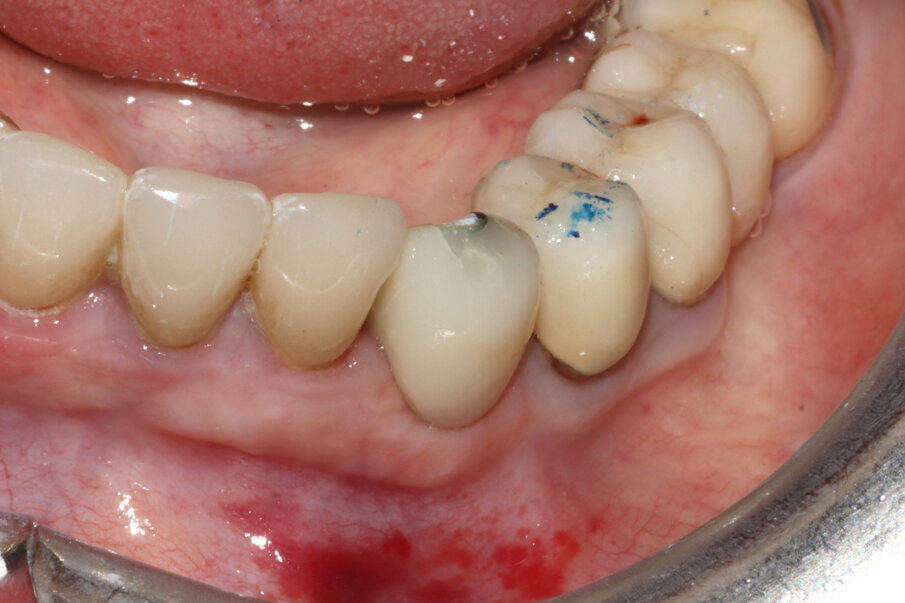

Fig. 3_Il caso clinico descritto: elemento 3.3 già rivestito di corona protesica, vitale e dolente.

Figg. 9-11_Inserimento dell’impianto e costruzione di una corona provvisoria. Si noti la forma a “C” dello shield e, al termine dell’intervento, la compostezza dei tessuti, gestiti senza alcun tipo di lembo.